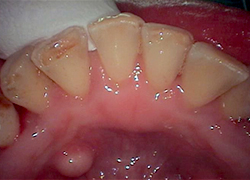

-

クリーニング前

クリーニング後